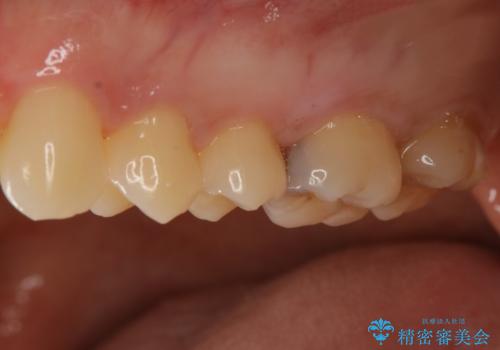

セラミックインレーは変色がなく耐摩耗性にも優れるため、長期的に良好な予後が見込める治療です。

セラミックインレー

歯の一部が虫歯になってしまった場合の治療法のひとつにインレーがあります。

虫歯になってしまった部分を含めて詰め物用に形を削り整え、型取りをし、出来上がってきた技工物をセメントで接着します。

自費治療では強度・色調・耐久性に優れたセラミックを使用した治療を選択する方が多いです。